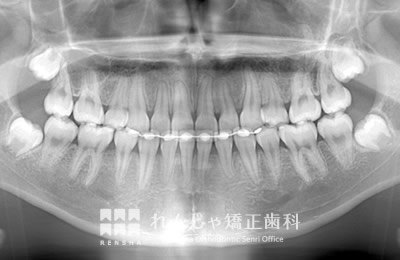

埋伏(まいふく)

永久歯が埋まったまま自然に萌出しないことがあります。周辺の歯に引っかかっていたり、歯胚(歯の卵)の位置や方向が悪い場合、分厚い歯ぐきに覆われている場合など様々です。埋伏している永久歯が隣接する永久歯の歯根を吸収してしまうこともあるので、引っ張り出す処置(牽引処置)が必要になることがほとんどです。場合によっては埋伏歯を抜歯してしまうこともあります。

他の永久歯に比べて生えてくるのが遅い場合(右上前歯は出たのに、左上は半年経っても出ない等)は注意が必要です。

右上5番目が埋まったままになっているため、スペースを作り引っ張り出しています。

治療前

| 主訴 | 前歯のがたつき |

|---|---|

| 診断名 | Angle Class II 上顎右側第二小臼歯の埋伏を伴う上顎前突 |

| 初診時年齢 | 10歳10か月 |

| 装置名 | マルチブラケット装置 |

| 抜歯非抜歯 | 非抜歯 |

| 治療期間 | 2年1か月 |

| 費用の目安 | 約41万円+消費税(検査料金、都度の処置費用等も合わせた総額) |

| リスク副作用 | 歯の移動に伴う軽微な歯根吸収、歯槽骨吸収、歯肉退縮(いずれも本症例ではほぼ無し)、矯正器具装着中のカリエスリスク増大(本症例ではカリエス発生無し) |